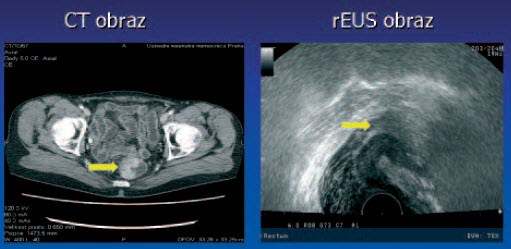

Tumor T3 N0

Tumor T3 N0 - kolonoskopie

Tumor T3 N0 po radioterapii - kolonoskopie